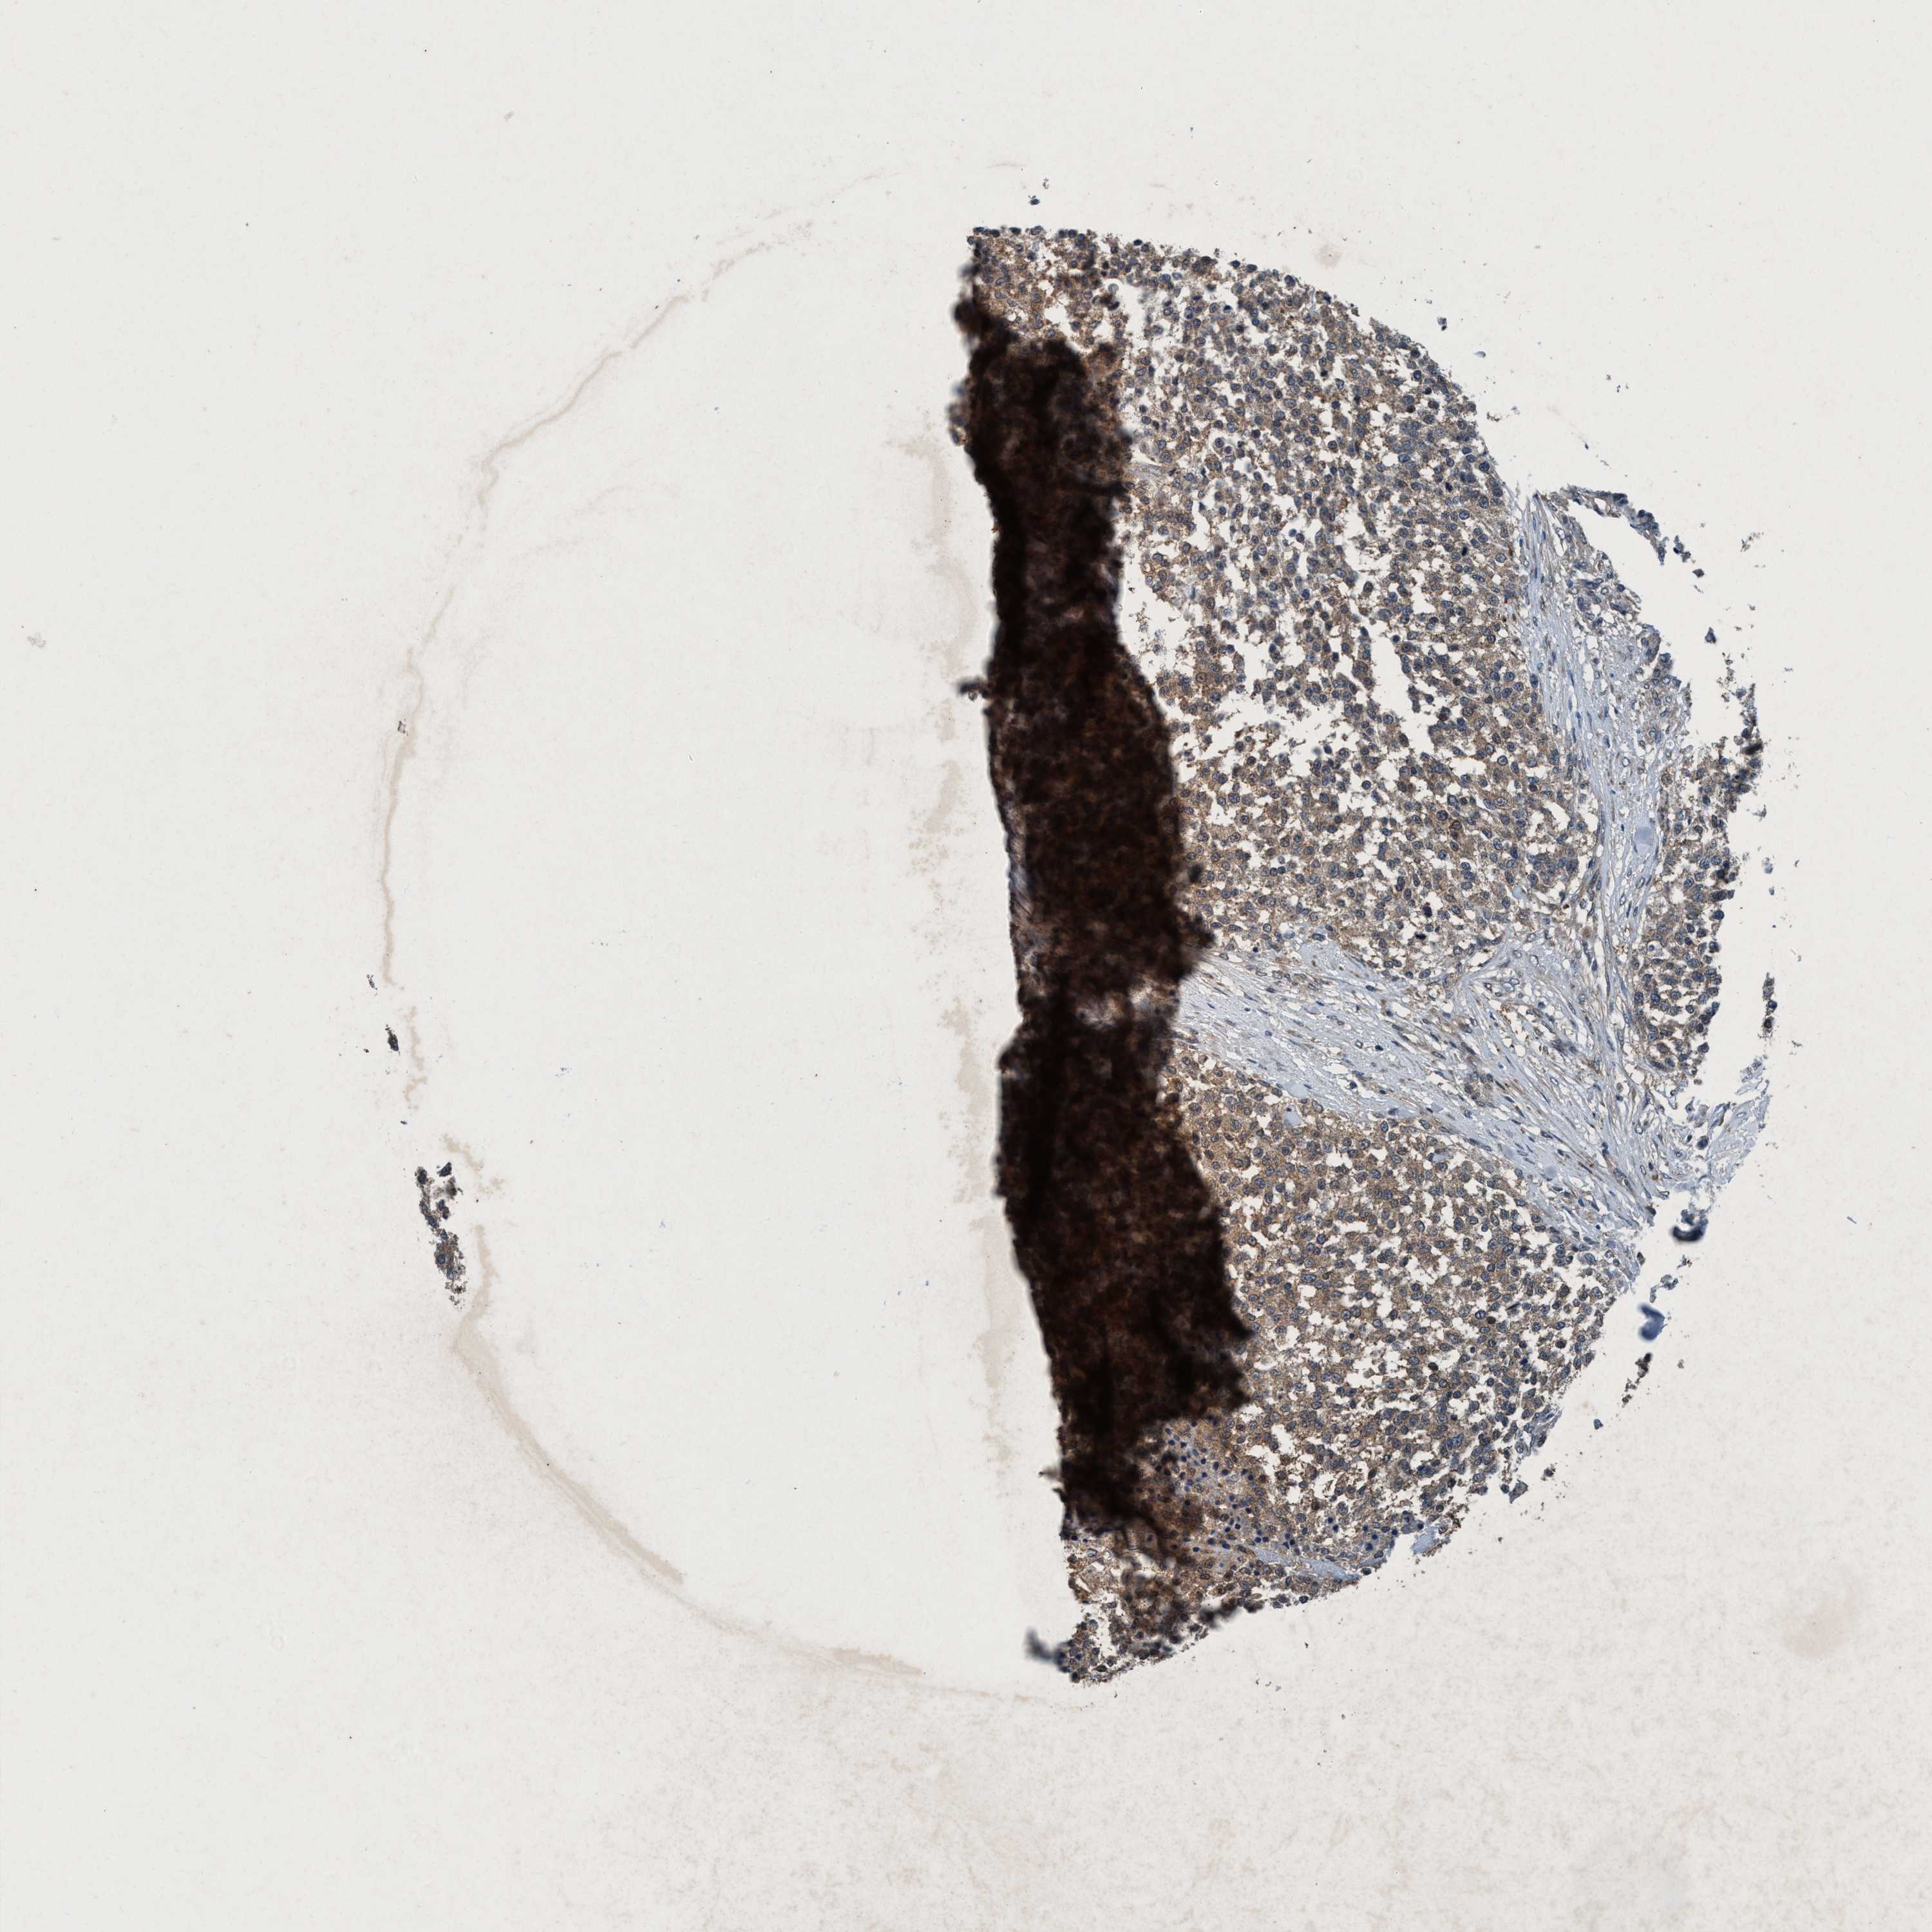

TESTIS CANCER - Protein expressioni

A mouse-over function shows sample information and annotation data. Click on an image to view it in a full screen mode. Samples can be filtered based on level of antibody staining by selecting one or several of the following categories: high, medium, low and not detected. The assay and annotation is described here.

Note that samples used for immunohistochemistry by the Human Protein Atlas do not correspond to samples in the TCGA dataset.

Antibody stainingi

Antibody staining in the annotated cell types in the current human tissue is reported as not detected, low, medium, or high, based on conventional immunohistochemistry profiling in selected tissues. This score is based on the combination of the staining intensity and fraction of stained cells.

Each image is clickable and will lead to virtual microscopy that enables deeper exploration of all samples and also displays staining intensity scores, fraction scores and subcellular localization as well as patient and tissue information for each sample.

Antibody HPA064427

Antibody HPA075510

Antibody CAB021903

Seminoma, NOS

Carcinoma, Embryonal, NOS

Teratoma, malignant, NOS